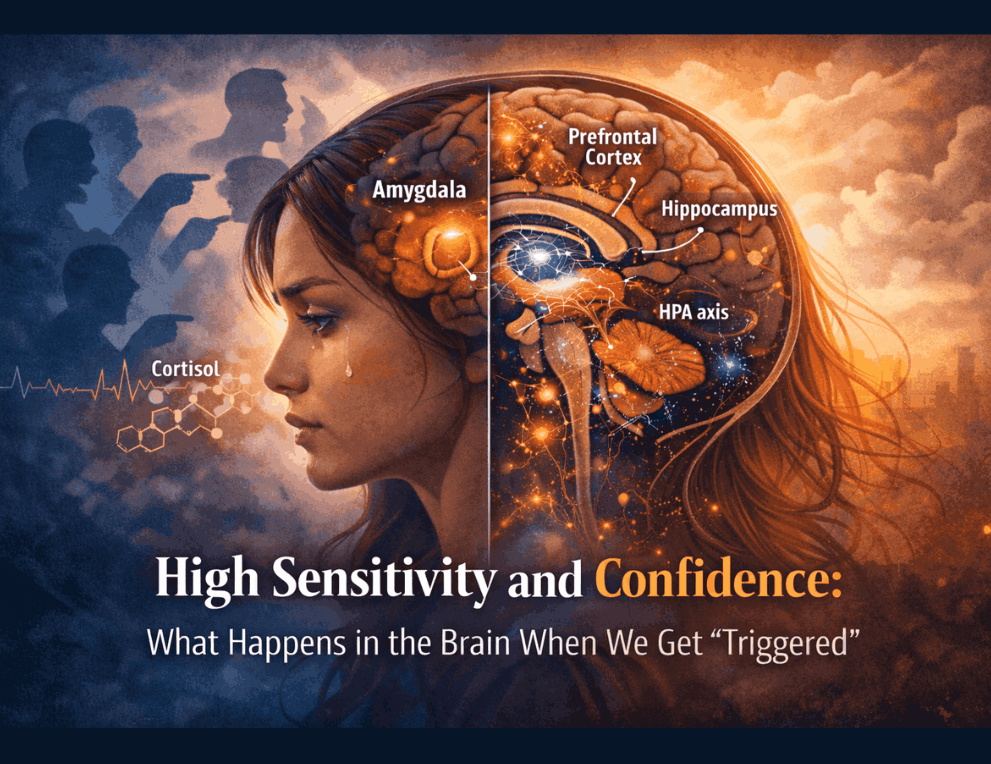

Коли ми отримуємо різке зауваження або стикаємося з осудом, першою реагує Амігдала — структура лімбічної системи, відповідальна за розпізнавання загроз.

Це не метафора. У 2003 році Naomi Eisenberger і Matthew Lieberman (UCLA) провели відоме дослідження Cyberball. Учасників “виключали” з віртуальної гри — форма соціального відторгнення. Томографія показала активацію таких частин мозку як:

Чому в моменті «вимикається голова»

Після активації амігдали запускається стресова реакція:

- підвищується кортизол

Тому так і виходить, що при гострому стресі тимчасово знижується активність Префронтальної кори — області, відповідальної за:

Нейробіолог Amy Arnsten (2009) описала, як стрес буквально “відключає” префронтальні функції, переводячи контроль до більш примітивних структур мозку.

В чому ж особливість високочутливих при стресових реакціях

Нейробіологічно це виглядає як сильніший зв’язок між префронтальною корою і амігдалою. Сигнал загрози виникає, але швидше регулюється.